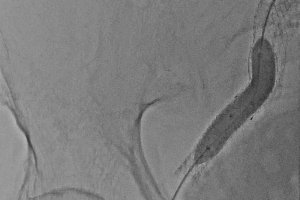

В экстренном порядке выполнено эндопротезирование наружной подвздошной артерии баллонорасширяемым стент-графтом Advanta V12 9х58 мм.